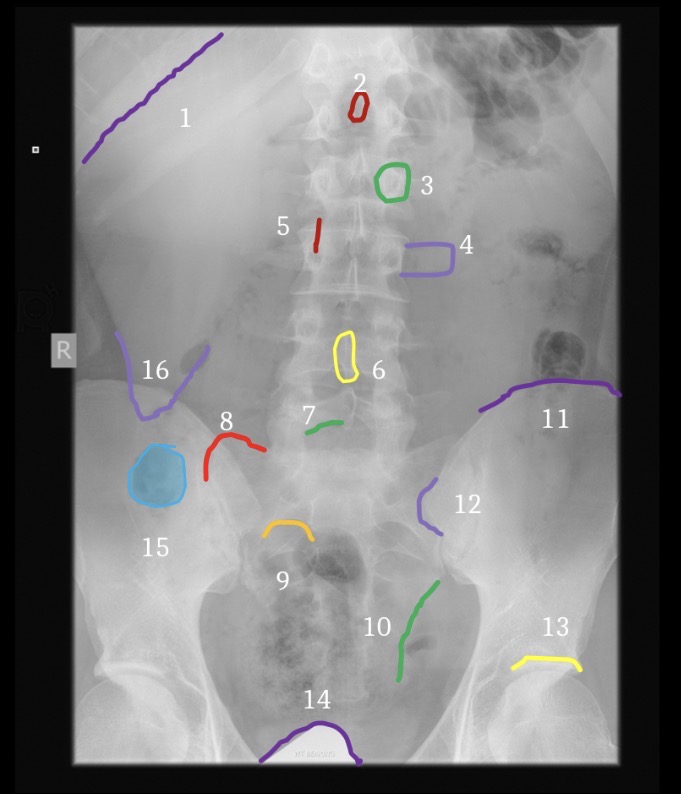

1

Inferior Margin of right 1th rib

2

Spinous process of T12

3

Left pedicle of L2

4

Left transverse process of L3

5

Right facet joint space L2-3

6

L4 spinous process

7

Inferior margin of right lamina L5

8

Right sacral ala

9

Superior margin right 1st anteror sacral foramen

10

Left margin of sacrum

11

Left iliac crest

12

Left posterior iliac spine

13

Superior margin left acetabulum

14

Gonadal shielding

15

Gas in colon

16

Inferior margin of liver